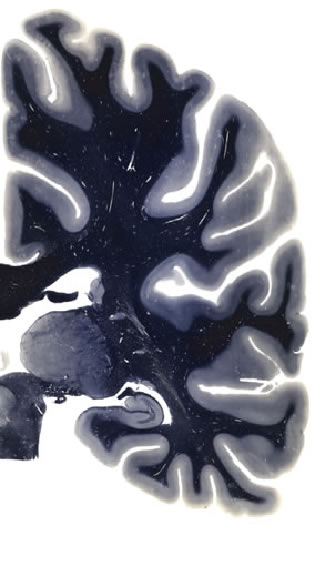

Hi-Resolution Sections · Cells (Nissl Staining) · Virtual Microscopy

Frontal sections (Nissl) from the Atlas Brain:

Slice ID:

r3-0205

Plate NR:

ca 46

Position:

31,8 mm